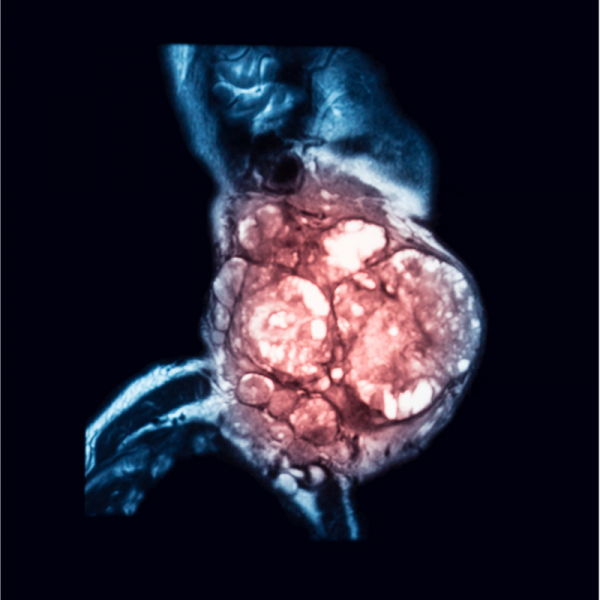

Krebs ist eine Krankheit, die weltweit Millionen von Menschen betrifft und deren Auswirkungen verheerend sein können. Die Diagnose Krebs kann ein Schock sein und stellt sowohl für Betroffene als auch für ihre Angehörigen eine enorme körperliche, emotionale und finanzielle Belastung dar. Während die konventionelle Krebstherapie in Form von Operation, Bestrahlung und Chemotherapie oft als Standardbehandlung angesehen wird, suchen immer mehr Menschen nach alternativen Behandlungsmethoden, um ihre Heilungschancen zu verbessern und die Nebenwirkungen der herkömmlichen Therapien zu reduzieren. Eine vielversprechende Option, die immer mehr an Bedeutung gewinnt, ist die begleitende Frequenztherapie.

Die Idee der Frequenztherapie basiert auf der Annahme, dass jede Zelle und jedes Organ im Körper eine eigene Schwingung oder Frequenz hat. Bei einer Krankheit wie Krebs ist diese Frequenz gestört, was zu einer Fehlfunktion der Zellen führt. Die begleitende Frequenztherapie versucht, diese gestörten Frequenzen mithilfe von elektrischen Impulsen oder elektromagnetischen Wellen auszugleichen und somit die Selbstheilungskräfte des Körpers zu aktivieren.

Die Anwendung von Frequenztherapie in der Krebstherapie ist nicht neu. Schon in den 1920er Jahren experimentierte der Arzt Royal Rife mit elektrischen Frequenzen, um Tumorzellen zu zerstören. In den letzten Jahren hat die Forschung in diesem Bereich jedoch erhebliche Fortschritte gemacht und immer mehr Studien belegen die Wirksamkeit der begleitenden Frequenztherapie bei der Behandlung von Krebs.